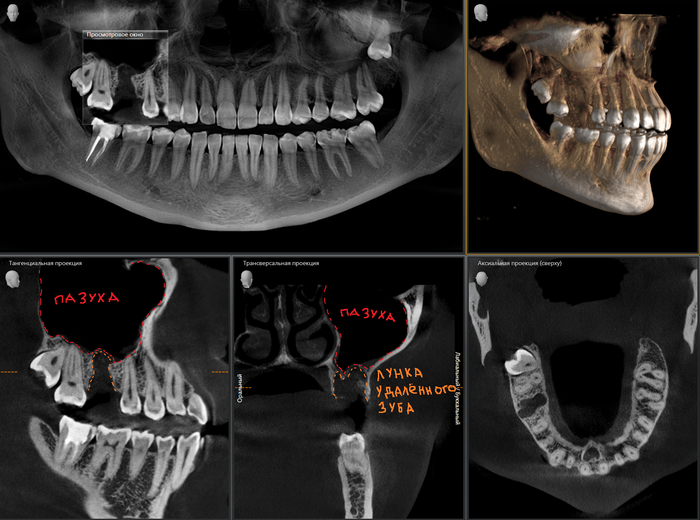

А теперь пример синус-лифтинга и имплантации, но через 2 месяца после того, как был удален 6-ой зуб на верхней челюсти. Этой пациентке удалили 6-ку около недели назад в другой клинике. Ассистентка сделала компьютерную томографию.

В связи с тем, что после удаления прошла всего неделя, то и на снимке мы видим «темную дыру», как ту, что оставила в твоем сердце бывшая. В том месте, где раньше был зуб. То есть костной ткани в этой области нет. К операции я приступил через 2 месяца. Повторную компьютерную томографию после заживления лунки делать не стали, но поверьте все зажило достаточно для того, чтобы можно было провести операцию. В ходе операции жесткой стабилизации имплантата добиться не удалось, поэтому я принял решение установить заглушку, а не формирователь десны. Почему? А потому, что если пациентка начнет грызть сухари, то на имплантат, в частности формирователь, может быть оказано сильное давление, в связи с чем имплантат может расшататься или «улететь» в пазуху. Заодно в утиль пошла и 8-ка.